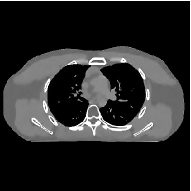

This section compares the reconstruction quality and runtime among the proposed MBIR method, PWLS-ST-, and other three MBIR methods, PWLS-EP, PWLS-DL, and PWLS-ST-. Table I shows that, for both 2D and 3D sparse-view CT reconstructions of the XCAT phantom, the proposed PWLS-ST- model outperforms PWLS-EP and PWLS-ST- in terms of RMSE. In addition, PWLS-ST- using a square transform (of size ) achieves lower RMSE than PWLS-DL using an overcomplete dictionary (of size ) for 2D sparse-view reconstructions. Fig. 3(a) and Fig. 4 show the reconstructed images for 2D and 3D phantom experiments, with different reconstruction models and different number of views. (See the corresponding error maps in the supplement.) The proposed PWLS-ST- consistently gives more accurate image reconstructions compared to other MBIR methods. Specifically, PWLS-ST- has smaller errors in the heart region (see zoom-ins in Fig. 3(a)) of 2D reconstructions than PWLS-DL and PWLS-ST-. In addition, compared to PWLS-ST-, PWLS-DL and PWLS-ST- have some ringing artifacts around the edges with high transition, e.g., edges between air and soft tissues. (See a comparison of profiles of PWLS-ST- and PWLS-ST- in the supplement.) In particular, PWLS-ST- and PWLS-DL give more visible ringing artifacts for 2D reconstruction from fewer views, and PWLS-ST- has these ringing artifacts for 3D reconstructions regardless of the number of views (see zoom-ins in Fig. 4). Table II reports runtimes of different MBIR methods in reconstructing the -views XCAT phantom scan. (FBPConvNet is a non-MBIR method and its runtime for processing a image is approximately one second with a TITAN Xp GPU.) While providing better reconstruction quality, the proposed Algorithm 1 of PWLS-ST- has shorter runtime compared to the algorithms of PWLS-DL and PWLS-ST- in Section III-A. Similar to the PWLS-EP algorithm, the reconstruction time of the PWLS-DL, PWLS-ST-, and PWLS-ST- algorithms can be further reduced by using ordered subsets [51].

Fig. 3(b) shows that when tested on the clinical scan data, the proposed PWLS-ST- method improves reconstruction quality in terms of noise and artifacts removal (e.g., see zoom-ins for soft-issue regions), and edge preservation (e.g., see zoom-ins for bone regions), compared to PWLS-EP and PWLS-ST-. Compared to PWLS-DL, PWLS-ST- achieves comparable image quality, but requires less computational complexity.

| (a) 2D fan-beam CT experiments |

| (b) 3D axial cone-beam CT experiments |

III-B3 Generalization Capability Comparisons between a “Denoising” Deep NN and the Proposed PWLS-ST- Method

This section compares the generalization capabilities between the proposed MBIR method, PWLS-ST-, and a denoising deep NN, FBPConvNet [14], that are trained from the phantom data; in particular, we tested the trained PWLS-ST- and FBPConvNet models to phantom and clinical scan data. The results in Fig. 6 show that the non-MBIR FBPConvNet method has higher overfitting risks, compared to the proposed PWLS-ST- MBIR method. When tested on clinical scan data, PWLS-ST- achieves much more accurate reconstruction, compared to FBPConvNet. See Fig. 6(b). When tested on phantom data, FBPConvNet generates more unnatural features as the number of views reduces, although it gives lower RMSE values compared to PWLS-ST-. See zoom-ins in Fig. 6(a). The FBPConvNet results above correspond to those in the recent work [16] that FBPConvNet [14] generated some unexpected structures.